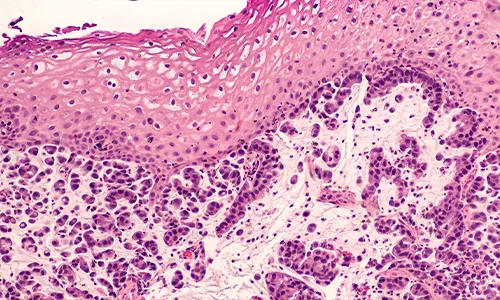

Esophagealcancer comes in two primary subtypes:

- Squamous cell carcinoma

- Adenocarcinoma